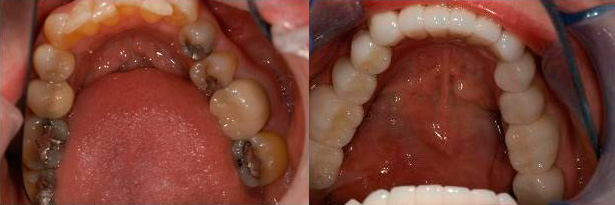

Лечение зубов во время беременности: фото до и после